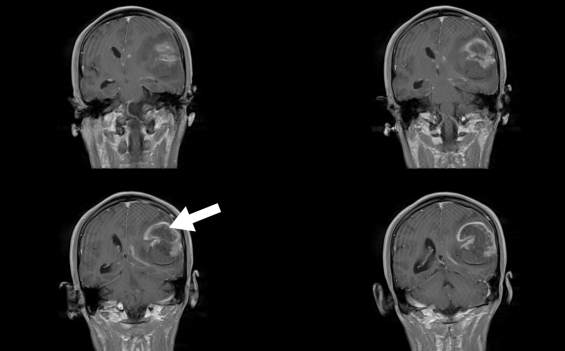

李大伯因左側(cè)肢體乏力4天到惠州三院神經(jīng)醫(yī)學中心門診就診,CT檢查提示:右側(cè)額頂葉腦水腫查因:腦腫瘤?隨后,李大伯入住神經(jīng)外科二病區(qū),醫(yī)生進一步完善檢查后發(fā)現(xiàn),李大伯患上右側(cè)額葉占位性病變!經(jīng)過手術(shù)治療后,李大伯情況好轉(zhuǎn),病理診斷是轉(zhuǎn)移瘤!

陳先生早晨起床時,突然感覺肢體無力,言語不清,站立、持物等活動受限。他被緊急送到醫(yī)院,急診ct檢查發(fā)現(xiàn)左側(cè)顳頂葉腦出血,并且疑似腫瘤出血。醫(yī)生進一步檢查發(fā)現(xiàn),患者顱內(nèi)巨大腫瘤并卒中(出血),情況十分危險,緊急開通綠色通道施行手術(shù)才保住了生命,病理診斷是膠質(zhì)瘤!